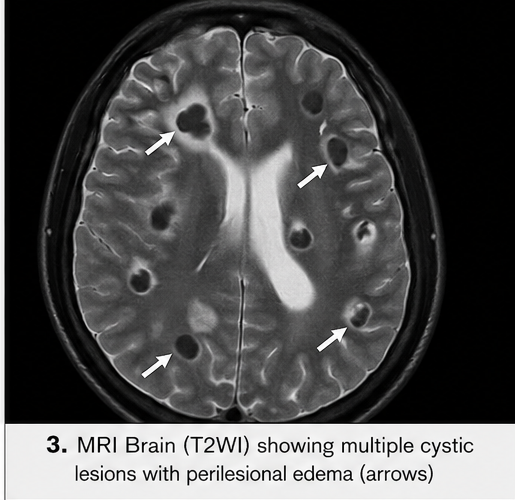

MRI Brain

• Multiple ring-enhancing lesions in the parietal and frontal lobes

• Lesions in different stages (vesicular and colloidal)

• Perilesional edema with mild mass effect

These findings were highly suggestive of neurocysticercosis.

• Repeat MRI showed reduction in lesion size

• Decreased perilesional edema

• Some lesions progressed to calcified stage

MRI is more sensitive for detecting viable cysts and ventricular involvement.